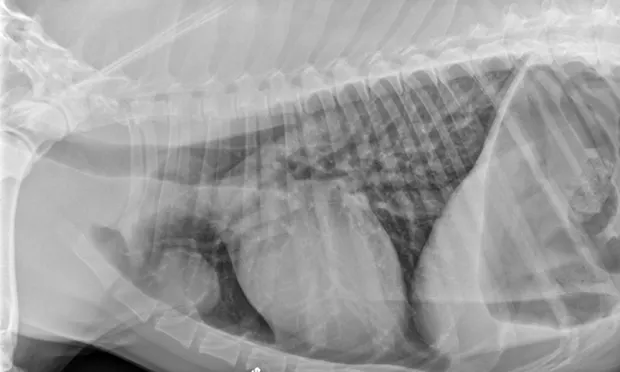

Thoracic radiography and abdominal ultrasonography were performed to screen for an inciting cause of MG. Thoracic radiographs (Figure 1) showed a well-circumscribed, spherical-to-ovoid cranial mediastinal mass and moderate megaesophagus. Thymoma was considered the most likely cause. There was no evidence of aspiration pneumonia. Abdominal ultrasonography was unremarkable.

Figure 1. Lateral (A) and ventrodorsal (B) thoracic radiographs showing a round, circumscribed mass in the cranial thorax and moderate megaesophagus.